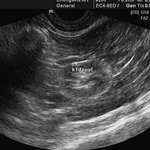

- 복부 초음파 검사

- 초음파를 통해 검사하는 복강 장기는 간, 비장, 췌장, 신장, 방광, 위와 소장/대장으로 이어지는 소화기관, 복강 내 림프절 등이 있습니다.

복부 초음파 검사는 혈액검사 상 발견된 이상과 더불어 장기 실질에 발생한 질병을 진단하는데 있어서 매우 유용한 방법입니다. 또한 초음파 탐촉자 가이드 하에 복수, 요 천자 검사를 비롯하여 각 장기와 종대된 림프절, 복강 내 종괴에 대한 정확한 원인 감별을 위해 초음파를 이용한 세침흡인검사를 진행하고 있습니다.